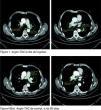

Ante la sospecha de TEP, se realizó directamente angio-TC donde se confirma la presencia de trombosis masiva bilateral que afecta a las ramas principales que se extienden hasta las segmentarias de ambos lóbulos inferiores con trombos de hasta 3cm (fig. 1). Se ingresa con tratamiento de heparina no fraccionada a dosis terapéuticas y se añade acenocumarol. No se observan complicaciones durante su estancia. Al alta, el paciente está asintomático, con saturación de 97%. Se continúa con anticoagulación oral y se le cita para un control de angio-TC a los 60 días, donde se aprecia la desaparición de las imágenes tromboembólicas (fig. 1).

Angio-TC el día del ingreso y de control a los 60 días.

Se presentan 2 tiras de imágenes. La primera tira corresponde a 2 imágenes de la angio-TC el día que ingresó el paciente en el hospital, y la segunda tira a otras 2 imágenes de la angio-TC de control que se realizó a los 60 días del primero.